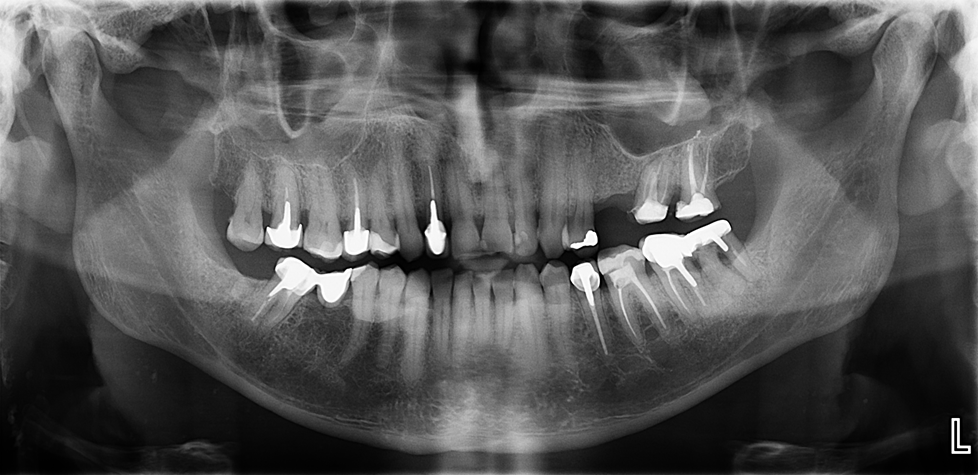

En la radiografía panorámica (Figura 1), se aprecia imagen radiopaca proyectada sobre tercio cervical y medio radicular de las piezas 36, 35, 34, 44, 45.

Radiografia Panorámica